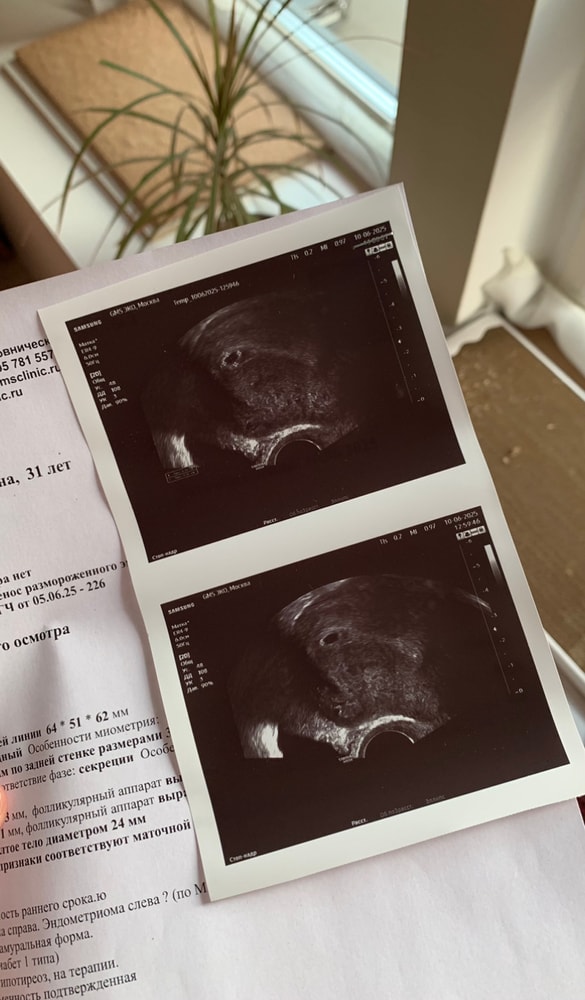

Котеночек прикрепиться в передней стенке матки, беременность маточная и это прекрасная новость 💛